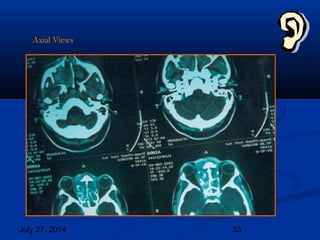

 C-T Scan (Nose andC-T Scan (Nose and

PNS)PNS)

 Obliteration of the nasal cavity, Rt.Obliteration of the nasal cavity, Rt.

Maxillary sinus, ethmoids with littleMaxillary sinus, ethmoids with little

extension into anterior cranial fossa.extension into anterior cranial fossa.

Lt. maxillary sinus is minimallyLt. maxillary sinus is minimally

affected.Destruction of Rt. Medialaffected.Destruction of Rt. Medial

orbital wall is also noted with littleorbital wall is also noted with little

extension into orbit.extension into orbit.

 Likely lesion could be NasalLikely lesion could be Nasal

polyposis, fungus. Howeverpolyposis, fungus. However

malignancy cannot be excluded.malignancy cannot be excluded.

Coronal Views

Axial Views